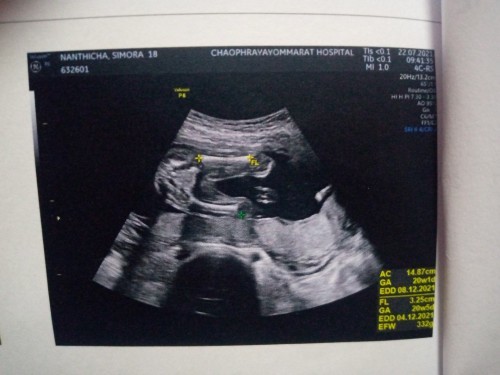

เดาว่า ผู้หญิง จ้าแม่ เพราะของเราน้องเป็นผู้ชาย ตอน 15 วีค ซาวด์ท่านี้ จะเห็นก้อนกลมๆตรงระหว่างขา โชว์ช้างน้อยให้เห็นชัดค่ะแม่

น่าจะผู้หญิงนะค่ะของเราได้ผู้ชายจ้านางโชว์ให้เห็นเลย

หญิงจ้าบ้านนี้เห็นแบบนี้เลยค่ะตอนนี้19วีคแล้ว

ผู้หญิงค่ะ น้องไม่มีไส้กรอกโพล่ออกมา

ผู้หญิงค่ะ ไม่มีจู๋😄